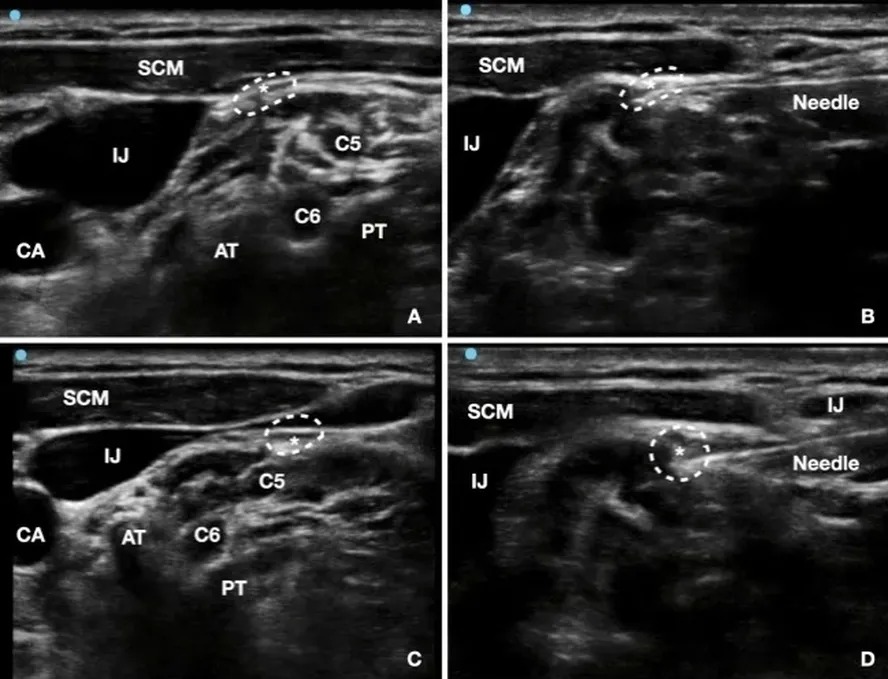

Depois disso, a equipe utilizou radiofrequência pulsada no nervo frênico, localizado no pescoço e responsável por atuar nos movimentos do diafragma. Nas semanas seguintes, os soluços começaram a diminuir e, em três meses, desapareceram completamente, de acordo com os autores do artigo. O texto médico informa ainda que não há uma causa única para o soluço, que pode ser desencadeado por fatores gastrointestinais, pulmonares ou pelo consumo de alimentos picantes.